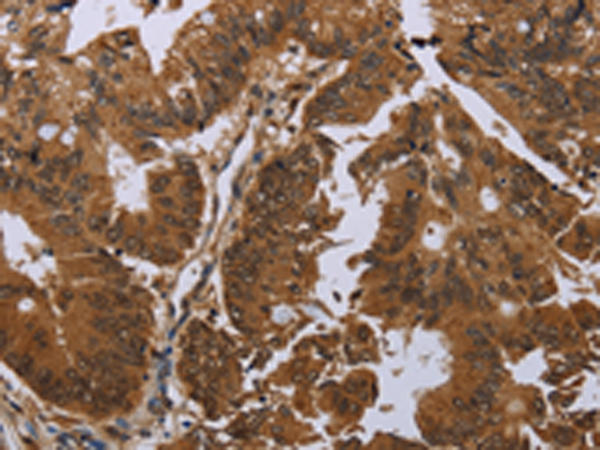

分类: 科研抗体货号: P11210别名:应用: IHC反应种属: Human, Mouse